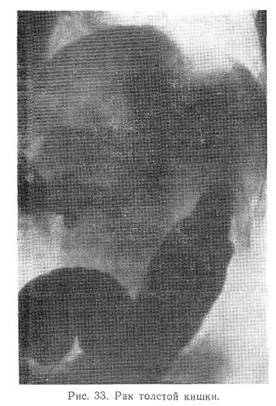

Существенное значение для диагностики имеет рентгенологическое исследование, в особенности метод ирригоскопии, а при раке сигмовидной и прямой кишок — ректороманоскопия.

Важнейшими рентгенологическими признаками являются длительная и стойкая задержка контрастной массы, дефекты наполнения с неправильными краями, постоянное сужение кишки, не поддающееся воздействию спазмолитических средств, патологический рельеф слизистой оболочки кишки, который лучше выявляется методом двойного контрастирования (наполнение кишки контрастной взвесью и после ее удаления — газом) (рис. 33).